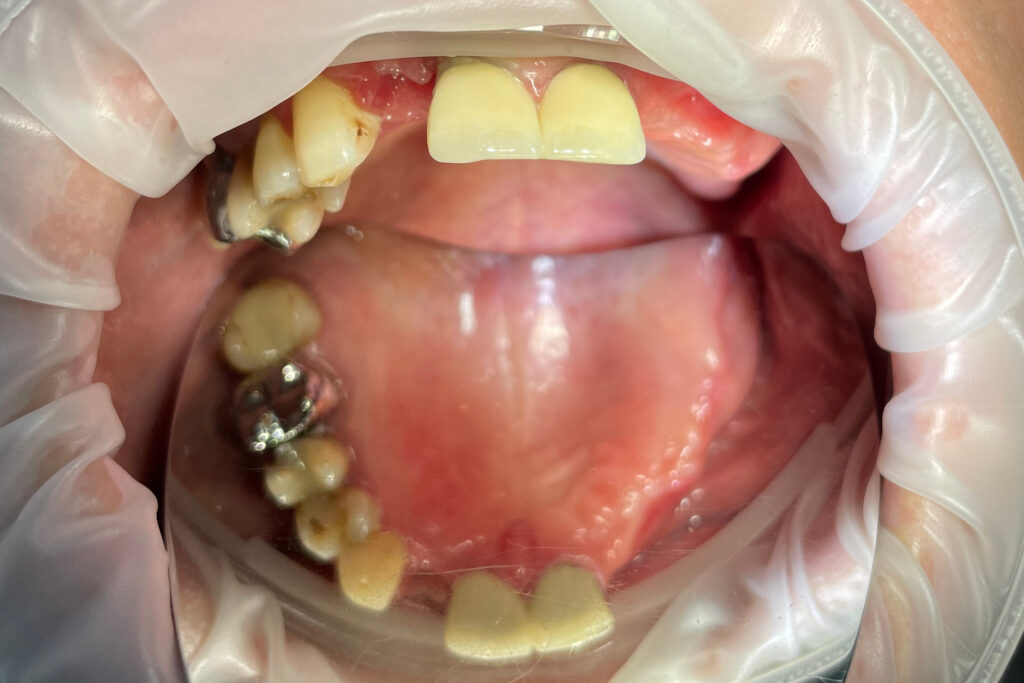

Ситуация до лечения

Жалобы: Пациент обратился к нам с целью проведения комплексной имплантации верхней челюсти.

Диагноз: Частичная вторичная адентия верхней челюсти.

пациент до протезирования

После консультации было принято решение об удалении зубов на верхней челюсти, которые находились в неудовлетворительном состоянии

и проведении комплексной имплантации по системе All-on-4.